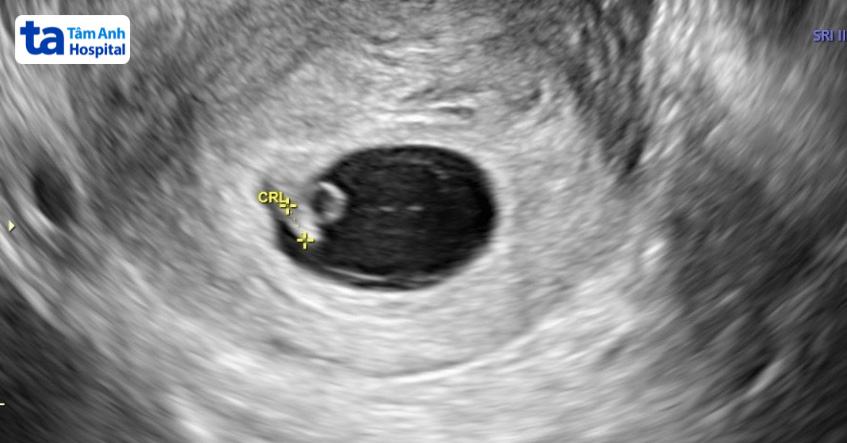

Khi có kết quả beta dương tính, siêu âm thai lần đầu tiên được thực hiện khoảng 3-5 tuần sau chuyển phôi (tương đương tuần tuổi thai thứ 5-7). Mục đích siêu âm để kiểm tra số lượng túi thai, vị trí thai, sức khỏe phôi thai và sự hiện diện của tim thai. Do đó chị em cần chờ ít nhất 21 ngày sau chuyển phôi để được siêu âm thai.

Siêu âm thai lần đầu tiên được thực hiện vào khoảng tuần thứ 3-5 sau chuyển phôi (tuần tuổi thai thứ 5-7) nhằm xác định người bệnh mang đơn thai hay đa thai, xác định vị trí làm tổ và kiểm tra sự hiện diện của tim thai.

Bác sĩ lưu ý đây là mốc siêu âm quan trọng mà chị em cần thăm khám theo chỉ định. Ở trường hợp siêu âm ở tuần tuổi thai thứ 6-7 chưa thấy tim thai, bác sĩ sẽ chỉ định siêu âm lại sau 1-2 tuần. (2)